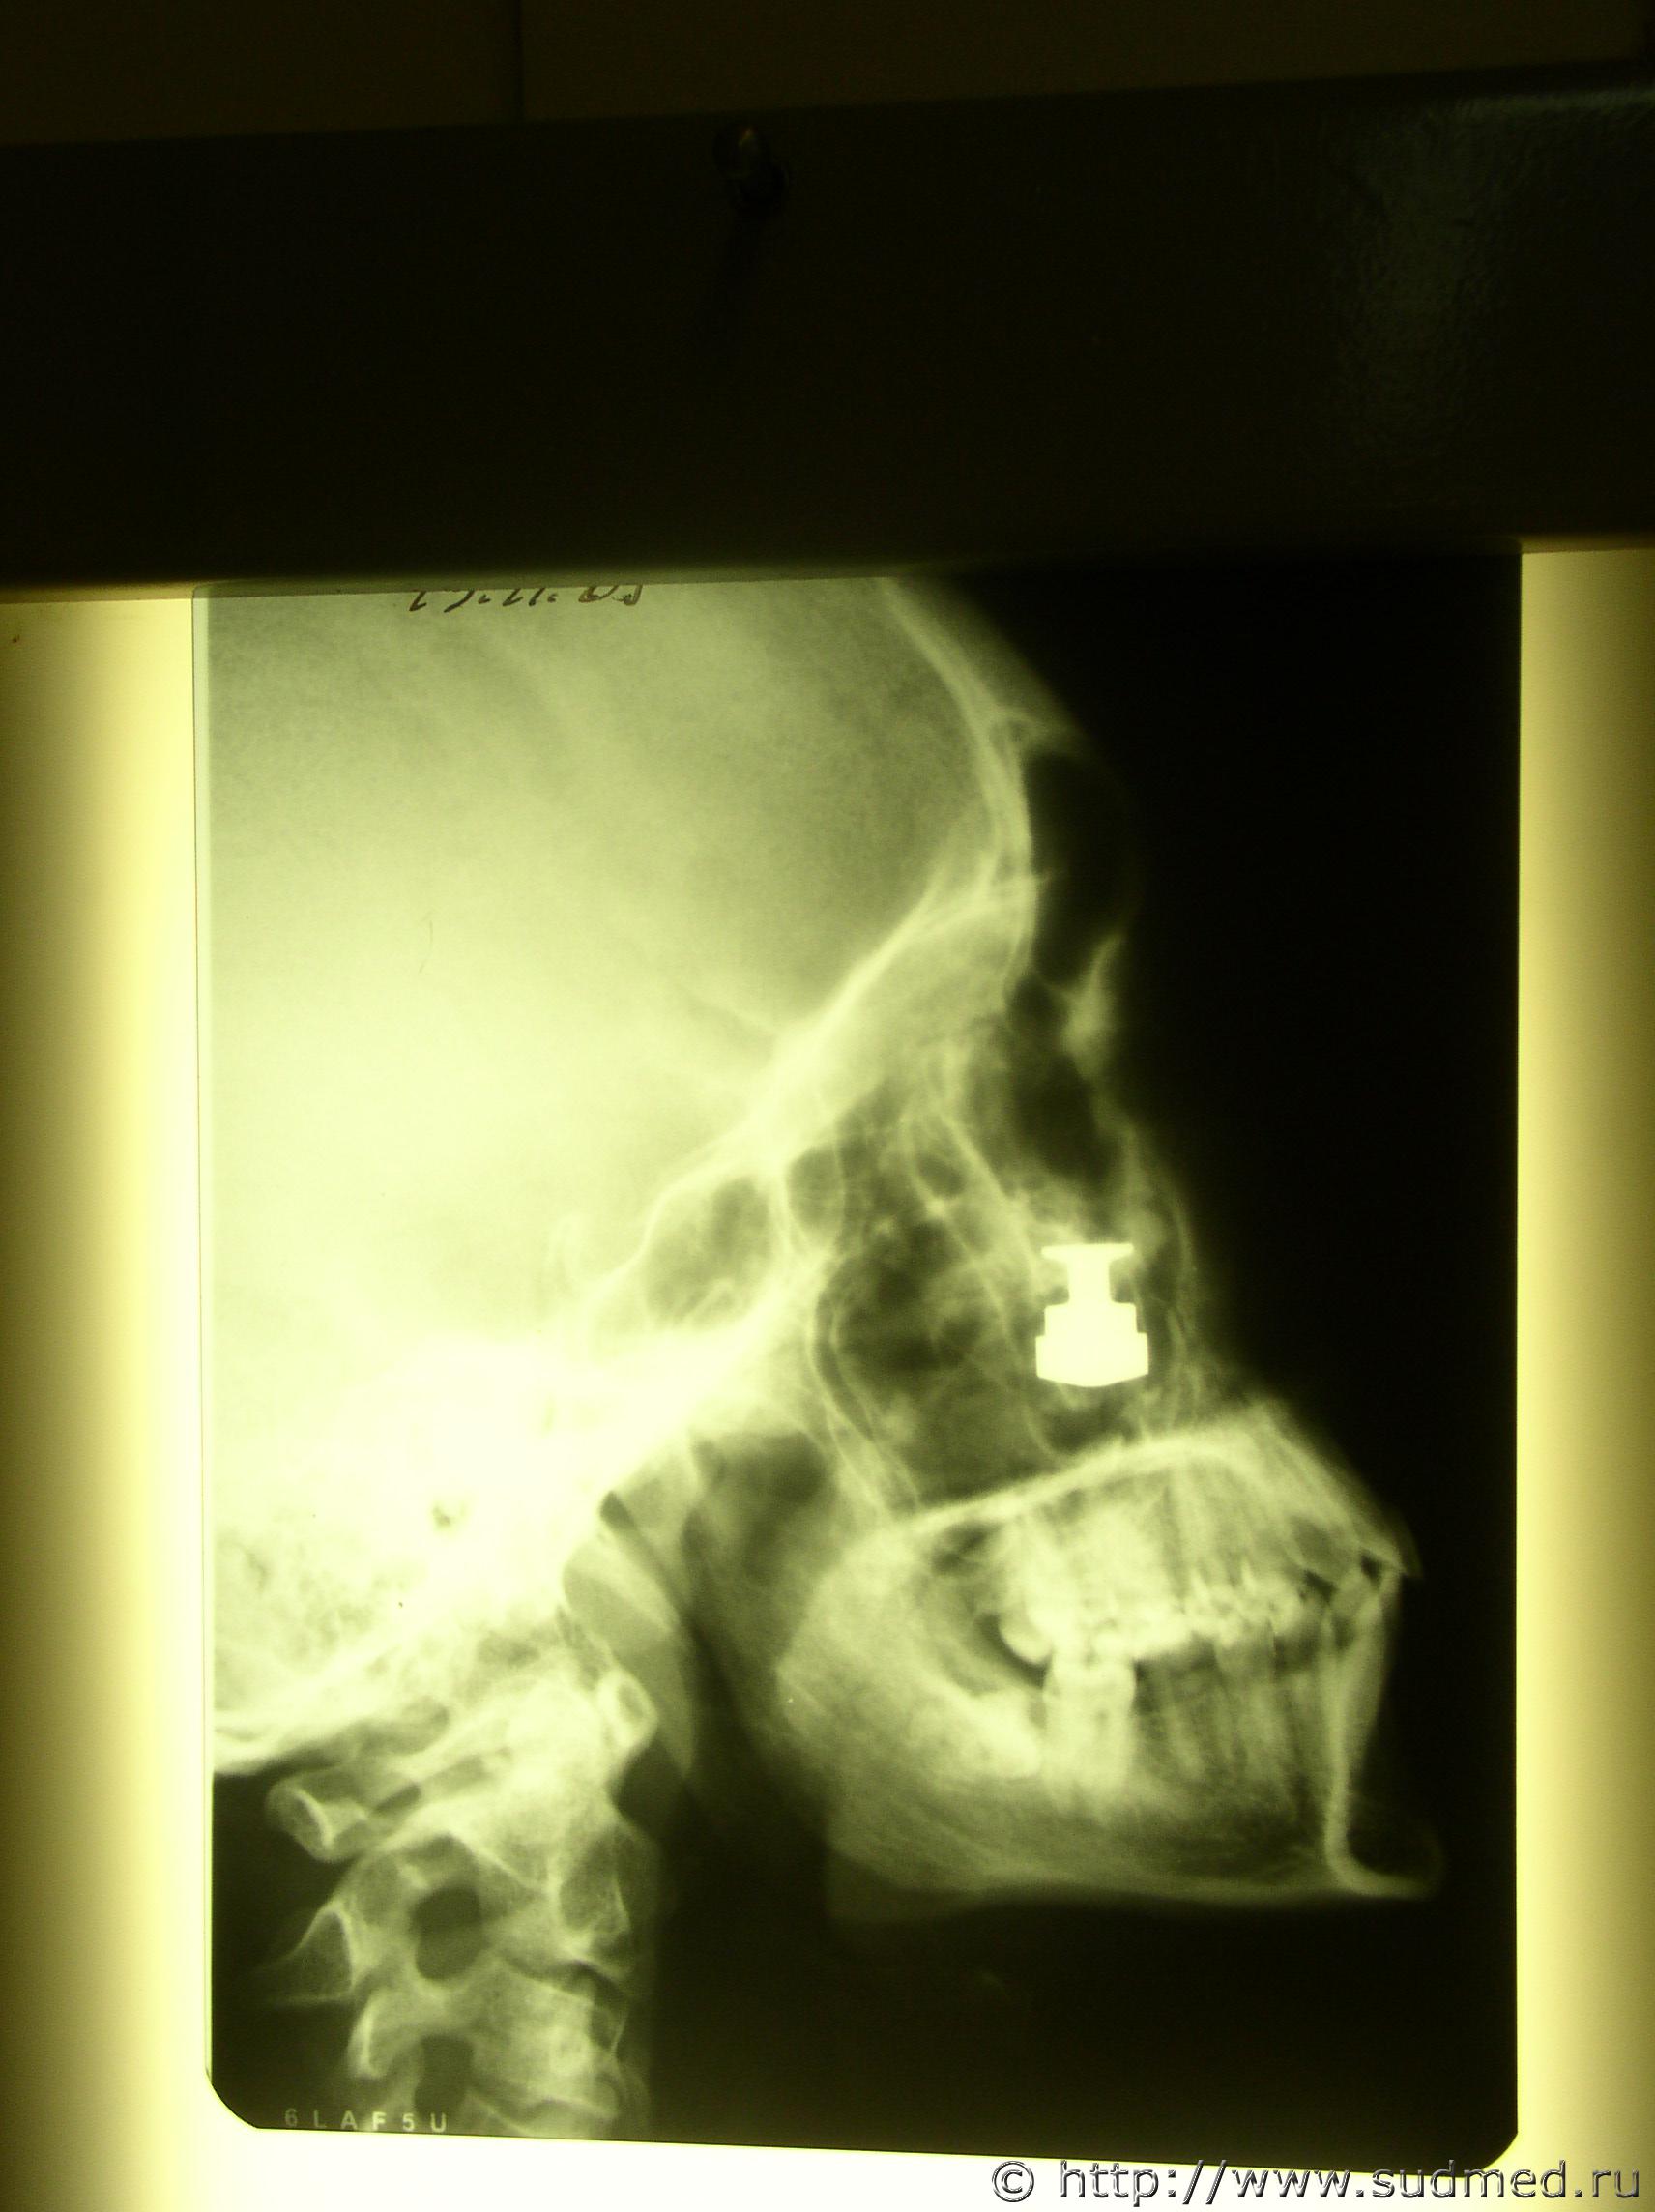

Пуля от "Осы" в мягких тканях лица.

Пуля от "Осы" реальная, была экспертиза по "живым" лицам, добавляю переднюю проекцию рентгена.

Судебная медицина - Прикрепленное изображение Судебная медицина - Прикрепленное изображение